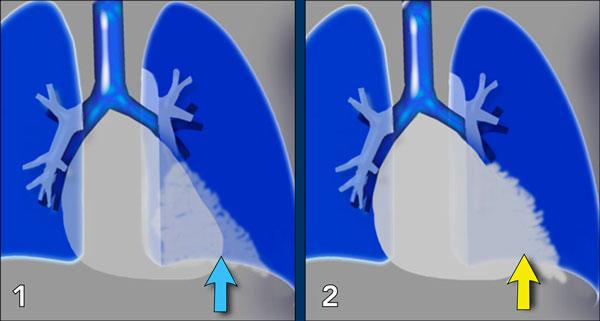

1. Không có dấu hiệu silhouette trong đám đông đặc ở thùy dưới trái (mũi tên xanh dương). 2. Dấu hiệu silhouette trong đám đông đặc ở thùy lưỡi (mũi tên vàng).

Dấu hiệu Silhouette

Dấu hiệu silhouette đề cập đến sự mất đường bờ bình thường giữa các cấu trúc có tỷ trọng X-quang khác nhau, thường gặp nhất là phổi chứa khí tiếp giáp với các cấu trúc phần mềm như tim hoặc cơ hoành.

Dấu hiệu này có vai trò quan trọng trong việc phát hiện các tổn thương kín đáo và định khu tổn thương trong lồng ngực.

Minh họa Dấu hiệu Silhouette

- Không có Dấu hiệu Silhouette (Mũi tên Xanh dương)

- Tâm thất trái, nằm ở phía trước, bình thường được tiếp giáp với thùy lưỡi chứa khí của thùy trên trái.

- Nếu đông đặc xảy ra ở thùy dưới trái (phía sau), ranh giới giữa thùy lưỡi và tim vẫn còn nguyên vẹn, và bờ tim trái được bảo tồn.

- Dấu hiệu Silhouette Dương tính (Mũi tên Vàng)

- Khi đông đặc hiện diện ở thùy lưỡi, vùng này tiếp giáp trực tiếp với bờ tim trái, làm mờ bóng của tâm thất trái.

- Điều này cho thấy tổn thương nằm ở phía trước lồng ngực.